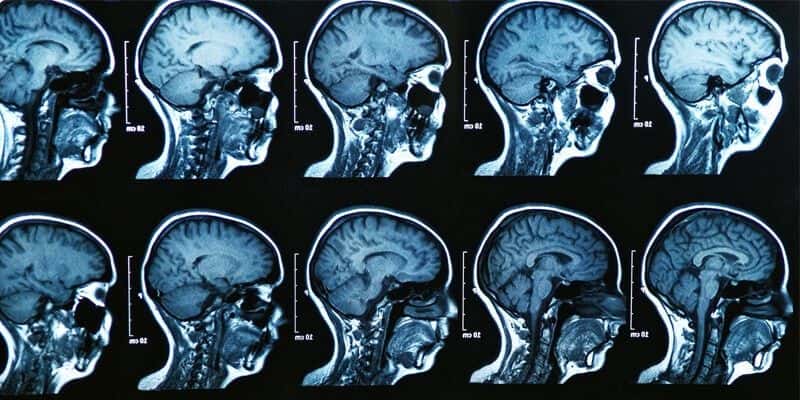

This case involves an 80-year-old male with a history of hypertension and paroxysmal atrial fibrillation. He had been off of the blood thinner Warfarin for several months when he presented to the emergency room with altered mental status. On initial exam, he was difficult to arouse with slurred speech and an expressive aphasia. A head CT was performed which did not reveal any acute intracranial abnormality. The primary differential diagnosis was an acute cerebrovascular accident due to the patient’s history of atrial fibrillation combined with his onset of neurologic deficits. A stat brain MRI was ordered but was not completed until the following day. In the meantime, the patient was admitted to the internal medicine service. Imaging revealed an acute infarct in the posterior temporal and occipital regions, bilateral cerebral peduncle infarcts, and a blot clot at the basilar terminus obstructing flow to the superior cerebellar arteries. The patient’s neurologic status continued to rapidly decline and he eventually succumbed to his injuries.